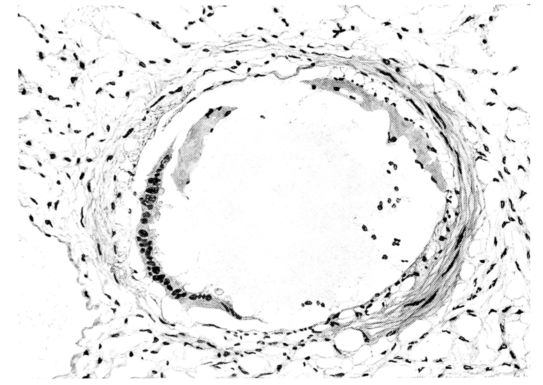

FIG. II. AUTOPSY NO. 98. DRAWING OF A SECTION THROUGH A TRACHEA SHOWING NECROTIZING HEMORRHAGIC INFLAMMATORY PROCESS OF THE MUCOSA.

The changes are less marked, perhaps, in the trachea than in its finer ramifications. The mucosa is constantly more or less destroyed and large areas, usually focal, are entirely devoid of their epithelial covering. This is replaced by a sparse exudate, composed largely of red blood cells, mucus, a small amount of fibrin, and nuclear fragments (Fig. II). It may dip into the submucosa for a short distance, but usually these indentures are associated with the ducts of the mucous glands into which the inflammatory reaction extends. A more striking feature than the exudate, however, is the edema and the congestion of the submucosa. The loose areolar tissue of the submucosa is spread widely apart, and throughout it distended blood vessels are very conspicuous. Occasionally such a vessel is broken and actual hemorrhage appears in the submucosa. Occasionally, too, the inflammation extends down the duct to the mucous gland itself, and here, also, aplastic inflammatory reaction is evident, inasmuch as the acini now stain intensely red with the cells undifferentiated from each other and specked here and there by broken remains of the dead nuclei (Fig. III). After the disease has continued for a short period, even at the end of five or six days, some regeneration of the epithelial lining may be seen (3) (Fig. IV). But despite this, the acute picture persists, and there goes on, side by side, an attempted repair characterized by epithelial regeneration and the same evidence of acute change. Since the lesion is essentially a superficial one, scars or contractures of any extent are not encountered in the trachea, even in examples of the disease that have ended fatally only after many weeks.[4]